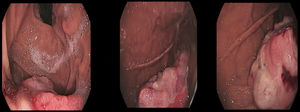

Varón de 79 años con antecedentes de melanoma en brazo izquierdo 3 años antes, tratado con cirugía y radioterapia, que es diagnosticado de adenocarcinoma de colon. En el estudio de extensión se objetiva la presencia de una lesión polipoidea de crecimiento predominantemente endoluminal en fundus gástrico de unos 5cm de diámetro sin signos aparentes de extensión transmural ni adenopatías regionales (fig. 1). Se realizó gastroscopia que confirmó la presencia de una lesión polipoidea en fundus, de unos 5cm, con áreas ulceradas e irregulares, sugestiva de malignidad (fig. 2), siendo la biopsia compatible con metástasis por melanoma. Se realizó hemicolectomía derecha laparoscópica más gastrectomía atípica.